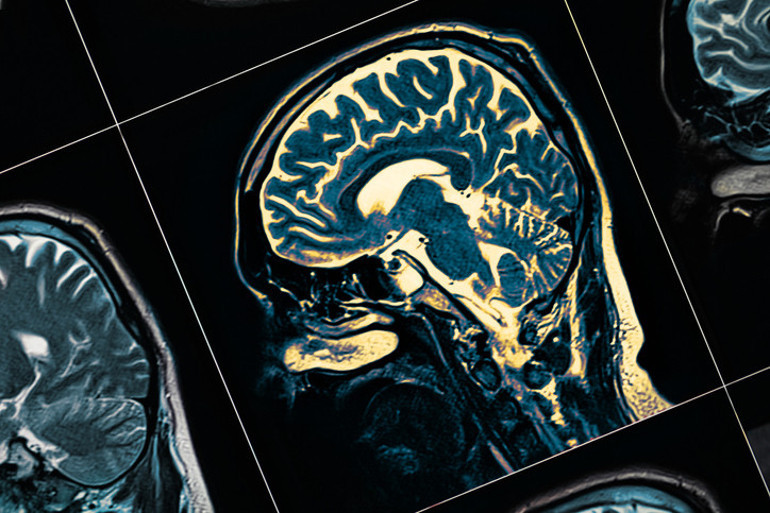

Dr. Lisa Mosconi, menopoz sırasında östrojendeki karakteristik düşüşün beynin bazı bölgelerindeki işleyişi değiştirmekle kalmayıp yapısını da değiştirdiğinin düşünüldüğünü söyledi.

Nitekim taramalar da aynı yaştaki erkek beyinlerine ve menopoz öncesi kadınların beyinlerine kıyasla menopozal beyinlerde hacmin azaldığını gösteriyor.